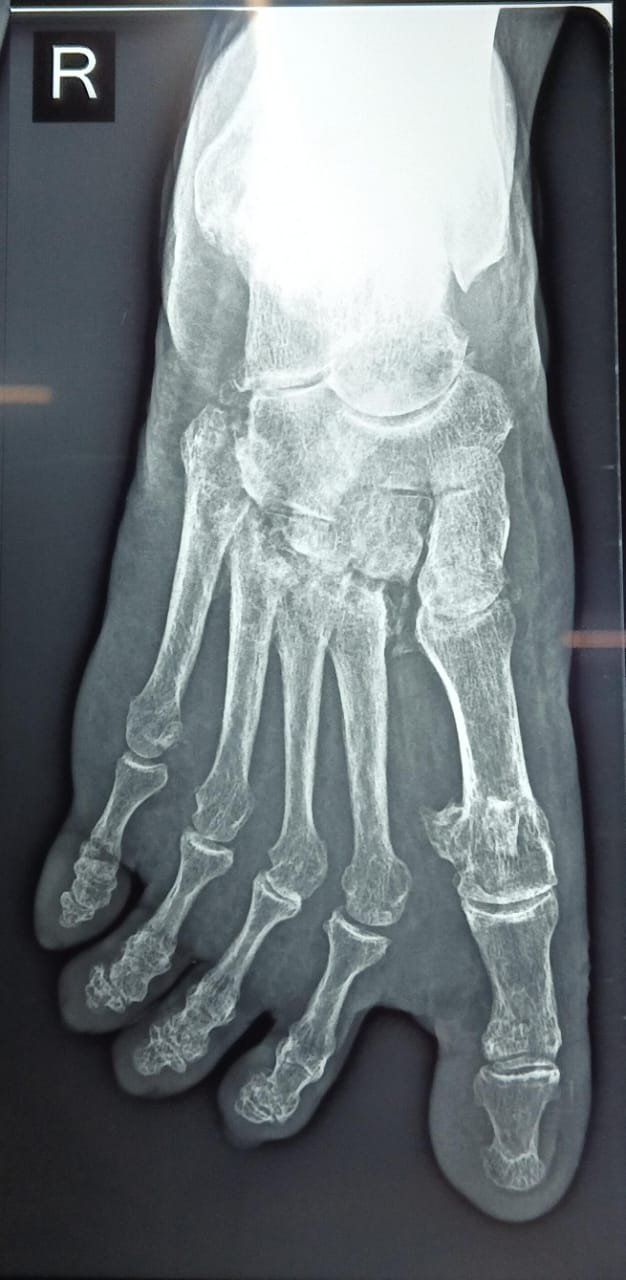

Lisfranc Injury

Atlas ID: 2 • Orthonotes Atlas

Lisfranc Injuries

Lisfranc Injury - Case Based Learning

Lisfranc Injury. Orthonotes Atlas. The Bone Stories. Available at: https://orthonotes.in/atlas/lisfranc-injury-69b949996a781 Accessed: 2026